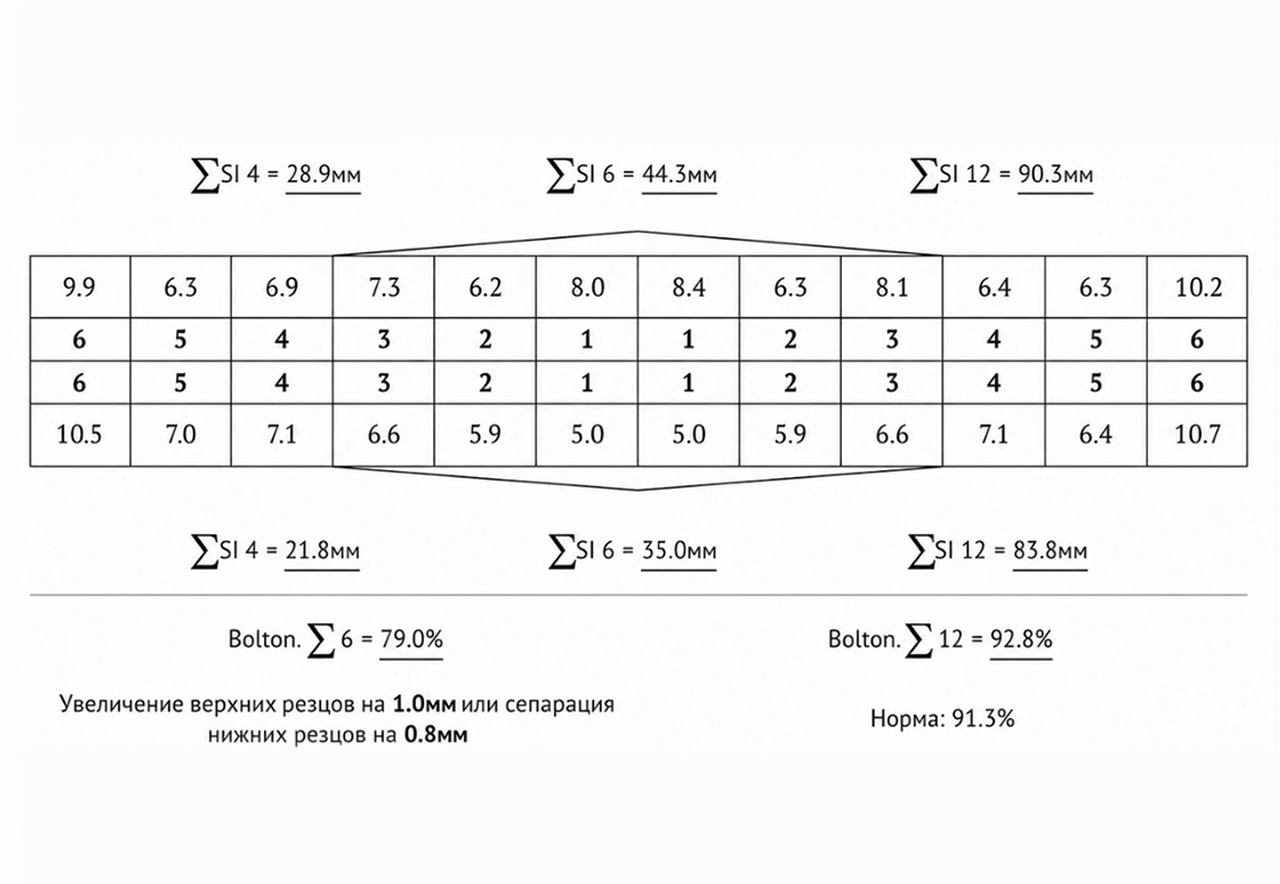

- С помощью специального программного обеспечения с математической точностью производим все рассчеты будущего лечения.

Будут произведены математические рассчеты будущего лечения